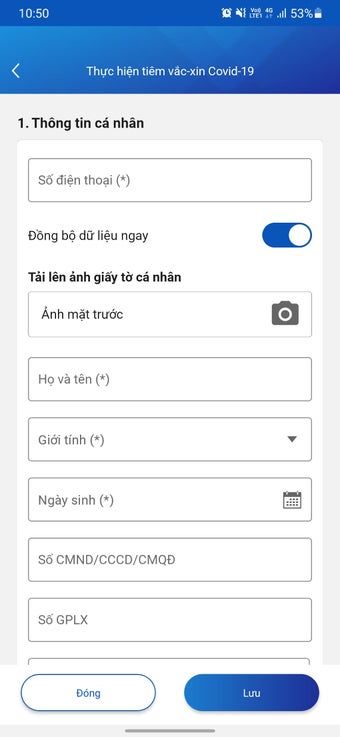

บันทึกข้อมูลสุขภาพอิเล็กทรอนิกส์สำหรับแพทย์เป็นแอปพลิเคชันแอนดรอยด์ที่พัฒนาโดย Văn phòng Bộ Y tế Việt Nam แอปพลิเคชันฟรีนี้ออกแบบมาเพื่อบุคลากรทางการแพทย์และแพทย์เพื่อเก็บข้อมูลผู้ป่วย ทำการฉีดวัคซีน เพื่อลดความแออัดที่จุดฉีดวัคซีน และลดความเสี่ยงในการติดเชื้อ COVID-19 นอกจากนี้ยังช่วยในการแก้ไขปัญหาสุขภาพของประชาชนอย่างรวดเร็ว

ด้วยบันทึกข้อมูลสุขภาพอิเล็กทรอนิกส์สำหรับแพทย์ บุคลากรทางการแพทย์สามารถวินิจฉัยและรักษาผู้ป่วยได้อย่างง่ายดาย โดยให้การดูแลสุขภาพอย่างครบถ้วนและต่อเนื่อง ตรวจจับโรคในระยะเริ่มต้น และให้การรักษาทันเวลา ซึ่งเป็นปัจจัยที่สำคัญในการเพิ่มประสิทธิภาพในการรักษาและลดค่าใช้จ่ายด้านสุขภาพสำหรับประชาชน